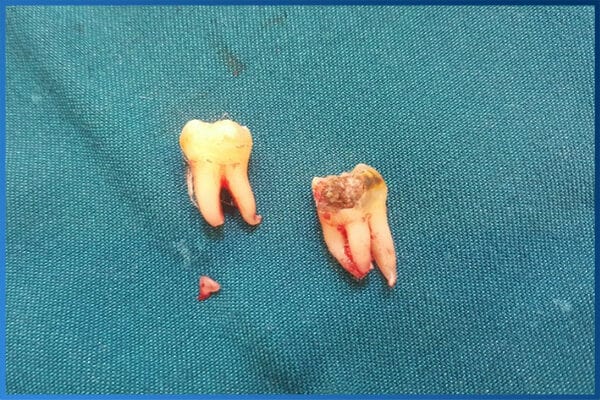

Nhổ răng khôn ở đâu an toàn tại quận Thanh Xuân Hà Nội